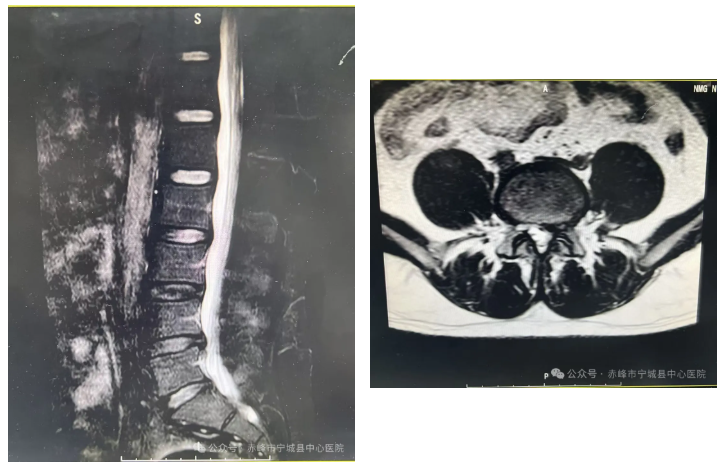

二:腰椎椎管狭窄症

术前影像